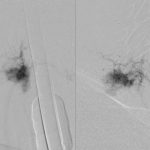

Ένα 24ωρό προ της επέμβασης στη Θωρακική Μοίρα, πραγματοποιήθηκε επιτυχώς εμβολισμός των συστοίχων αρτηριών υπό εξειδικευμένου επεμβατικού ακτινολόγου.

- α

- β

- γ

Εικόνα 9: Εμβολισμός των αρτηριών στο επίπεδο της περιοχής Θωρακικής Μοίρας της Σπονδυλικής Στήλης που πρόκειται να υποβληθεί σε χειρουργική επέμβαση. Κατά τον εμβολισμό διαπιστώθηκε ότι η αιμάτωση της πρόσθιας νωτιαίας αρτηρίας γίνεται από την Θ11 μεσοπλεύριο δεξιά. Η αιμάτωση του όγκου γίνεται από τις μεσοπλεύριες αρτηρίες Θ8 και Θ9 άμφω.

Εχει επιτευχθεί εμβολισμός σε ποσοστό 80-90%. Την επομένη, πραγματοποιήθηκε η επέμβαση. Χάρις στον εμβολισμό των αγγείων και τα ειδικά φάρμακα (Τρανσαξεναμικό οξύ Tranexamic acid) που ελέγχουν την απώλεια αίματος, η αιμορραγία ήταν εξαιρετικά περιορισμένη και παρά τον χαμηλό αιματοκρίτη της ασθενούς, η επέμβαση διεκπεραιώθηκε ομαλά.